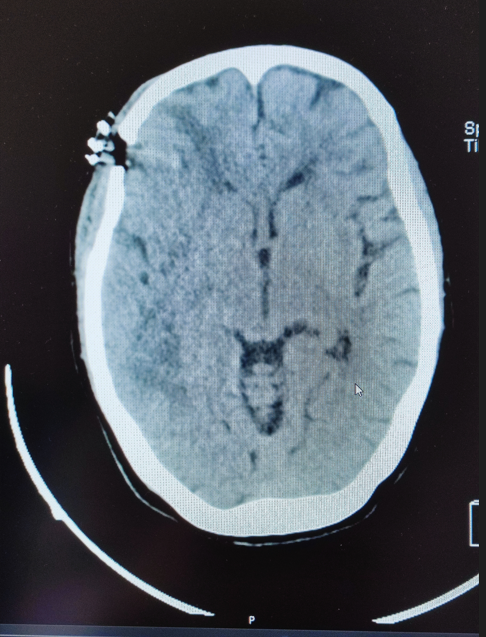

The patient underwent a neuronavigation-guided stereotactic biopsy without immediate complications. Postoperative imaging identified a small intratumoral hemorrhage without mass effect (Figure 2). Histopathological examination confirmed a diagnosis of high-grade glioma consistent with an IDH-wild-type glioblastoma. Treatment was promptly initiated with dexamethasone to reduce peritumoral edema and levetiracetam for seizure prophylaxis.

Figure 2 Stereotactic biopsy with minor hemorrhage.